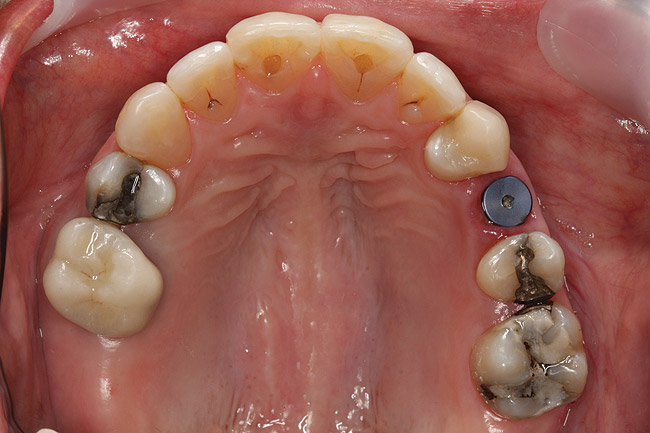

Fig 18 (through Fig 21). Note lack of alveolar development from congenitally missing Nos. 24 and 25. Surgical procedures after 5 months of orthodontic alignment included single-tooth osteotomies Nos. 6 to 11 and Nos. 21 to 28 and buccal corticotomies on all other teeth. Anchorage plate was stabilized to piriform rim.

Figure 18

Fig 20. Note lack of alveolar development from congenitally missing Nos. 24 and 25. Surgical procedures after 5 months of orthodontic alignment included single-tooth osteotomies Nos. 6 to 11 and Nos. 21 to 28 and buccal corticotomies on all other teeth. Anchorage plate was stabilized to piriform rim.

Figure 20

Fig 21 (and Fig 20). There is significant lateral dentoalveolar expansion of arches and alveoloskeletal correction in maxillary and mandibular anterior regions. Alveolar bone volume was increased in lower anterior to create optimal implant sites and establish ideal interincisal function and stability.

Figure 21